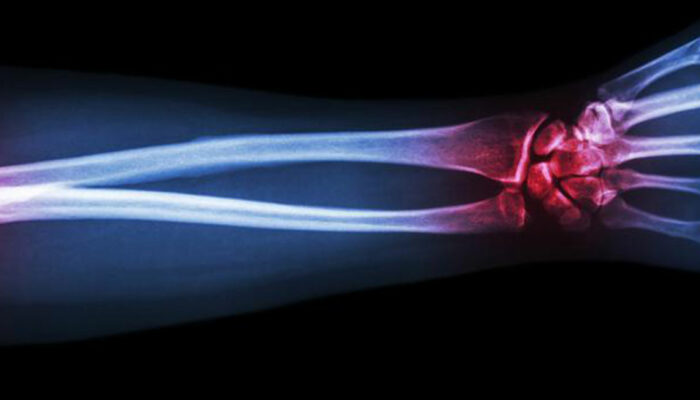

Gout is a type of arthritis that primarily attacks the joints and other body parts like the ears, wrists, knuckles, knee, ankles, and other small joints. It is often characterized by painful swelling, stiffness, and inflammation of these affected joints. The swelling and stiffness are mainly the results of excess levels of uric acid forming crystals in the joints.

The deposition of uric acid crystals in the joint causes inflammation and makes the movement of the joint agonizing. The elevated levels of uric acid in the system also causes the depositing of crystals in the kidney, which, in turn, leads to stone formation.